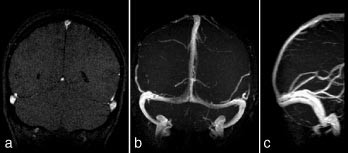

Intrakraniale kar

Kontrastforsterket MRA har foreløpig for dårlig romoppløsning for intrakranialt bruk. Den MRA-metoden som er best egnet for fremstilling av intrakraniale arterier, er 3D-innstrømnings-MRA (fig 3). Ved hjelp av denne metoden kan man påvise stenoser og okklusjoner av de større arteriene. Både MRA og CT-angiografi kan fremstille intrakraniale aneurismer med diameter på 5 mm eller mer med stor nøyaktighet (10, 11), for mindre aneurismer synes CT-angiografi å være noe bedre enn MRA. De ikke-invasive metodene kan bidra ved planlegging av behandling av aneurismer (kirurgisk eller radiologisk intervensjon), men metodene har ennå ikke kunnet erstatte kateterangiografi (12). Ved intrakraniale arteriovenøse malformasjoner er MR-snittbilder den metoden som best viser den anatomiske lokaliseringen av nidus (13). MRA kan gi en bedre anatomisk oversikt over hele malformasjonen, særlig om man benytter fasekontrast-MRA, som gir best fremstilling av både arterie- og venesiden. Både kirurgi og endovaskulær embolisering krever imidlertid en detaljfremstilling som bare kan gis av kateterangiografi.